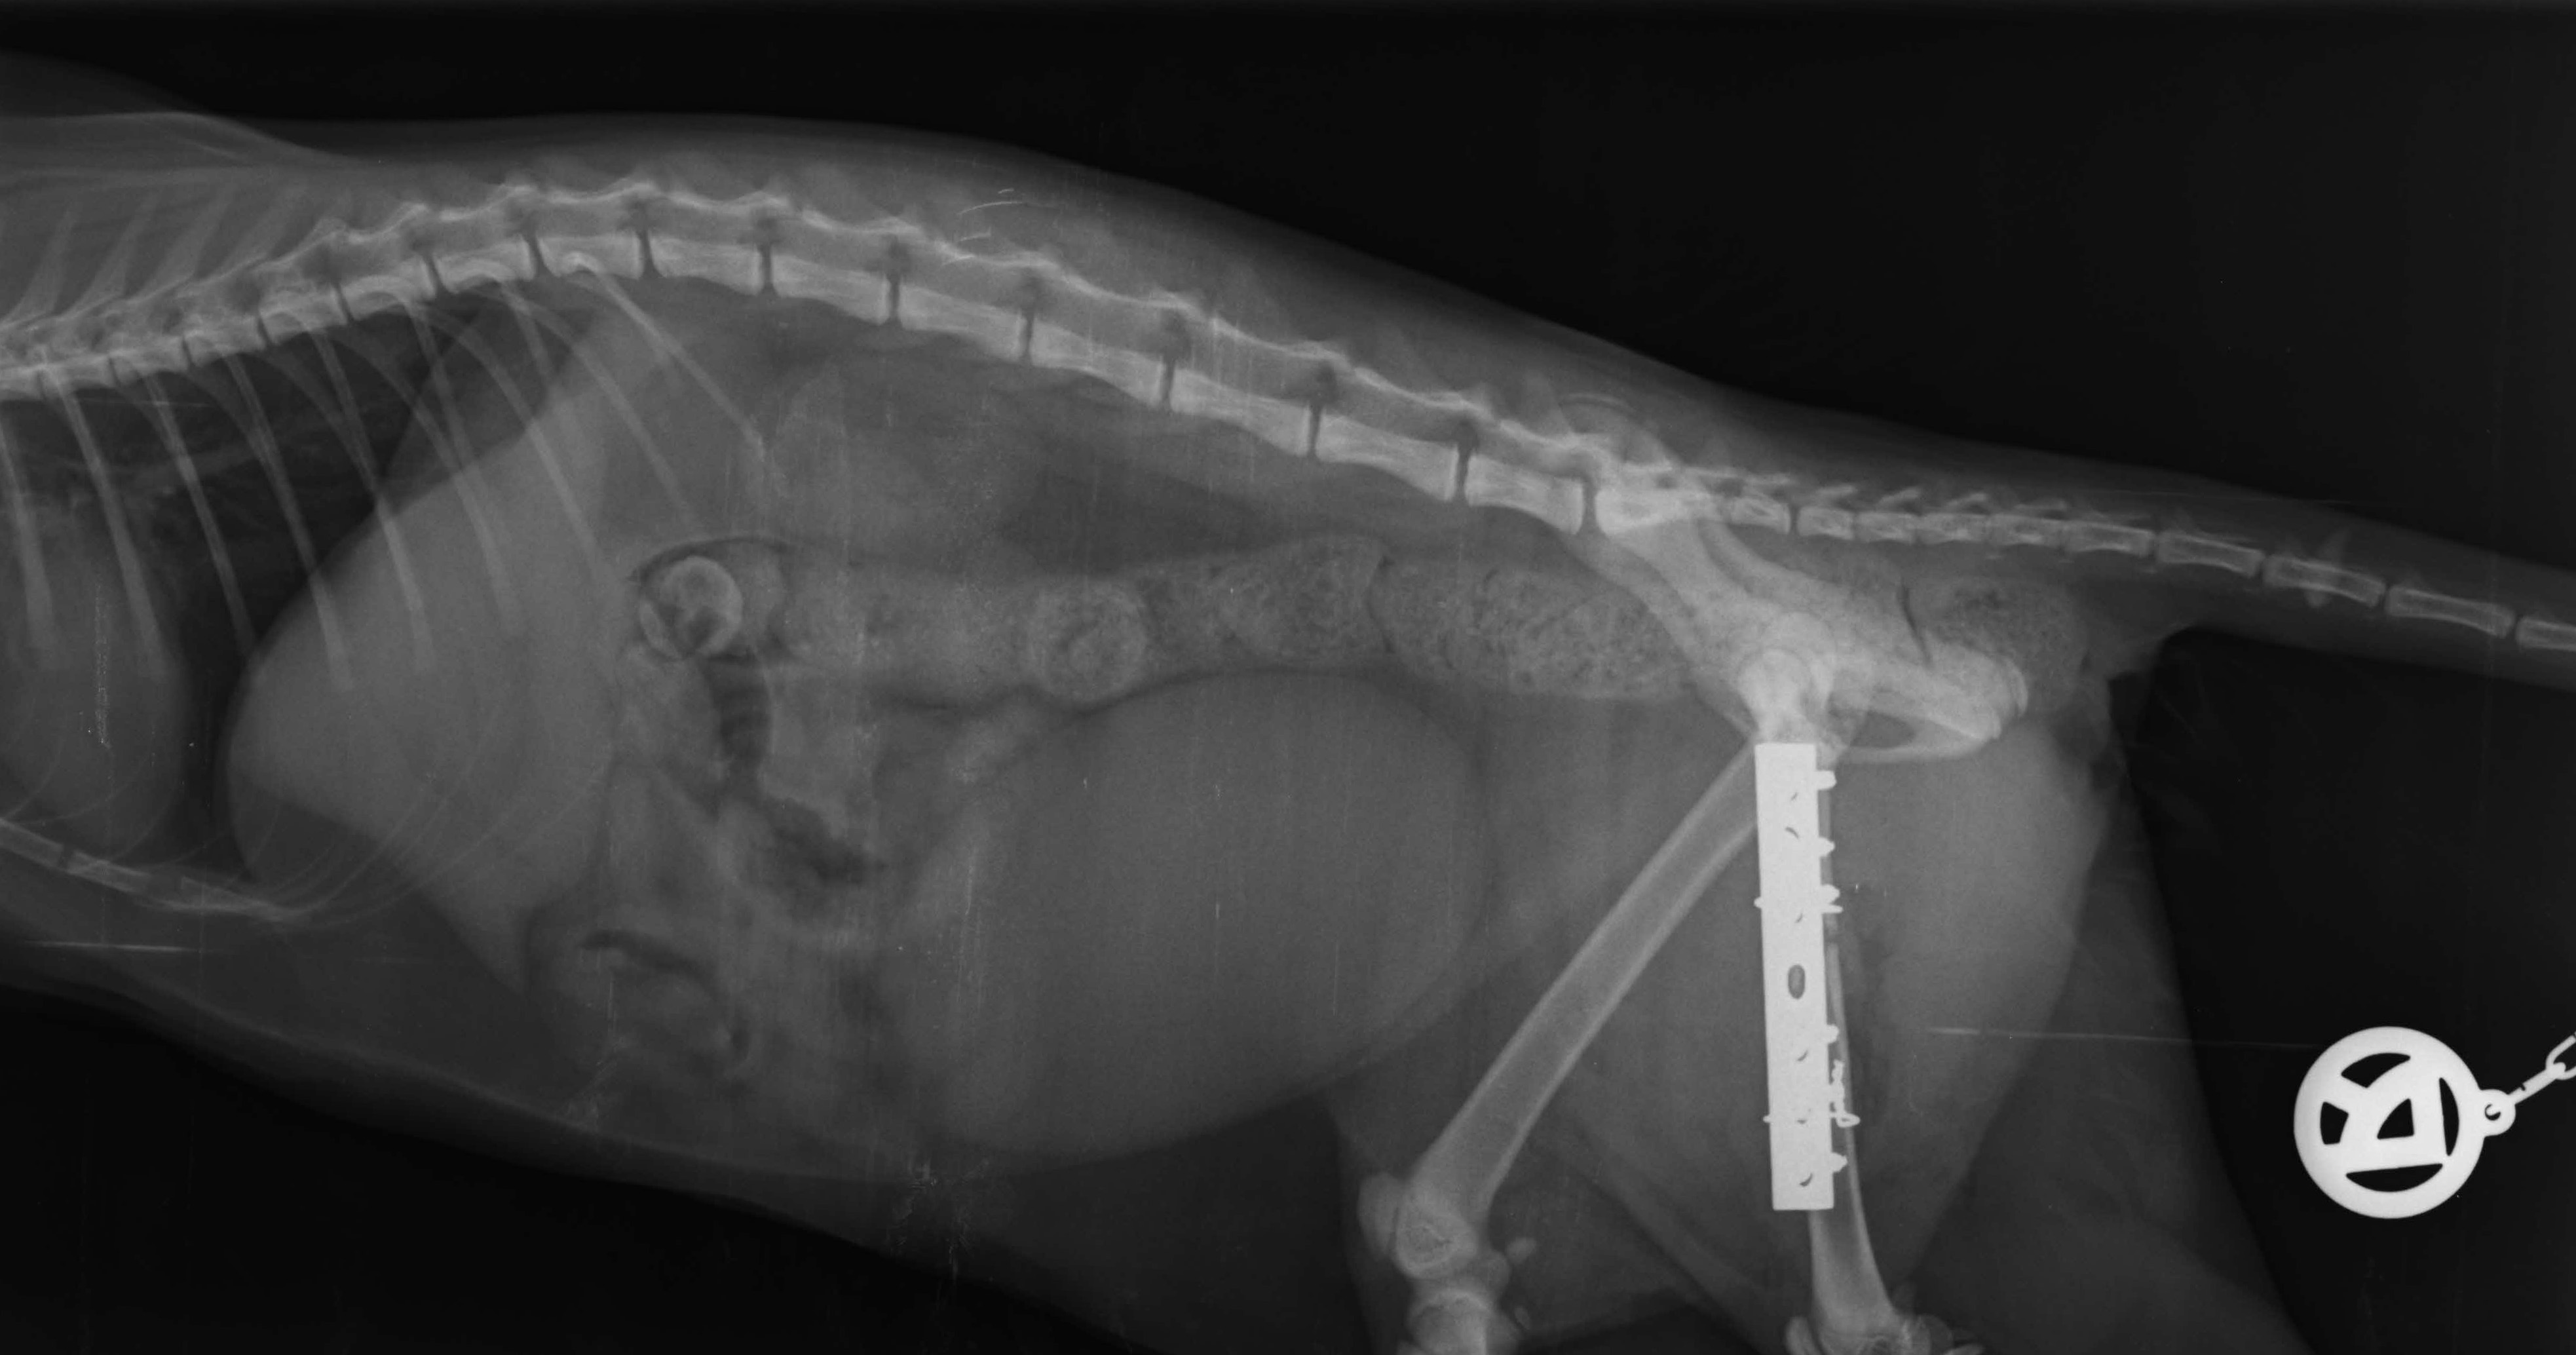

Röntgen, Ultraschall und auch die Endoskopie gehören bei uns zu den bildgebenden Diagnosemethoden, die routinemäßig angewendet werden. Viele Erkrankungen lassen sich erst durch diese weiterführenden Untersuchungen zweifelsfrei feststellen.